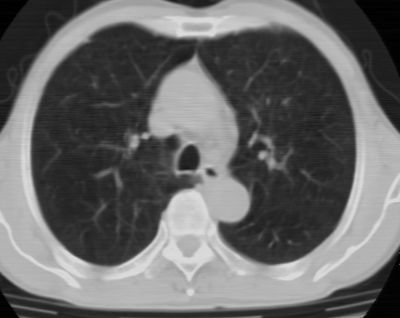

标题: CT24783:m71,既往肺心病史3年,现咳嗽,憋喘。 [打印本页]

标题: CT24783:m71,既往肺心病史3年,现咳嗽,憋喘。

1、左肺上叶spn,毛刺+分叶+血管集束征,考虑周围型肺癌可能性大

2、全小叶性肺气肿。

1)左肺上叶周围型肺癌可能。2)两肺全小叶型肺气肿。

左上周围型肺癌,全小叶型肺气肿。